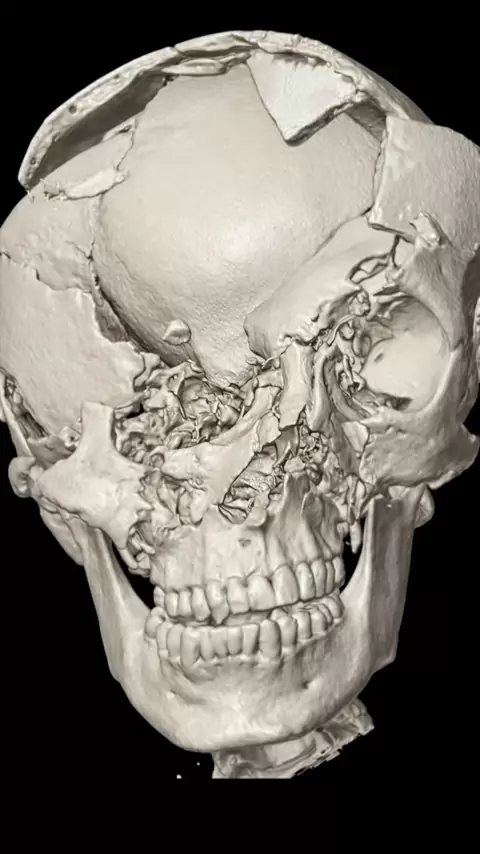

Does your facility do Post Mortem CT scans? Do you feel it's necessary or waste of resources? #postmortem #ctscan #radiology #xray #cttech Image Credit: Reddit

Kraniotomi adalah prosedur bedah saraf di mana sebagian tengkorak (tempurung kepala) diangkat sementara untuk memberikan akses ke otak Tujuan kraniotomi adalah untuk memperbaiki atau menyingkirkan masalah pada otak, seperti tumor, bekuan darah, atau gangguan otak lainnya. Setelah prosedur selesai, bagian tengkorak yang diangkat akan dipasang kembali atau bisa juga tidak langsung dipasang kembali (kraniektomi). Kraniektomi adalah operasi pengangkatan sebagian tulang tengkorak untuk mengurangi t...